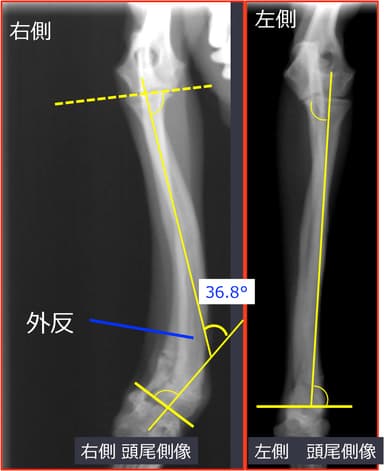

・前足は、横方向に36.8°外側へ向き(外反変形)、前後方向に10.2°手前に曲がっていた(前屈変形)。

術前X線画像1

http://www.atpress.ne.jp/releases/54567/img_54567_2.jpg

術前X線画像2

http://www.atpress.ne.jp/releases/54567/img_54567_3.jpg

1. 変形矯正を計画

・側面像(矯正前26.8°を17.6°へ)

・正面像にて(矯正前36.8°を3.5°へ)